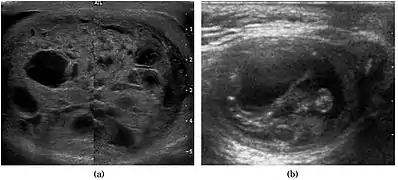

Teratoma Although teratoma is the second most common testicular tumor in children, it affects all age groups. Mature teratoma in children is often benign, but teratoma in adults, regardless of age, should be considered malignant. Teratomas are composed of all three germ cell layers, i.e. endoderm, mesoderm and ectoderm. At ultrasound, teratomas generally form well-circumscribed complex masses. Echogenic foci representing calcification, cartilage, immature bone and fibrosis are commonly seen [Fig. 5]. Cysts are also a common feature and depending on the contents of the cysts i.e. serous, mucoid or keratinous fluid, it may present as anechoic or complex structure [Fig. 6].

- Fig. 5. Teratoma. A plaque-like calcification with acoustic shadow is seen in the testis.

- Fig. 6. Mature cystic teratoma. (a) Composite Image. Mature cystic teratoma in a 29-year-old man. Longitudinal sonography image of the right testis shows a multilocular cystic mass. (b) Mature cystic teratoma in a 6-year-old boy. Longitudinal sonography of the right testis shows a cystic mass containing calcification with no obvious acoustic shadow.